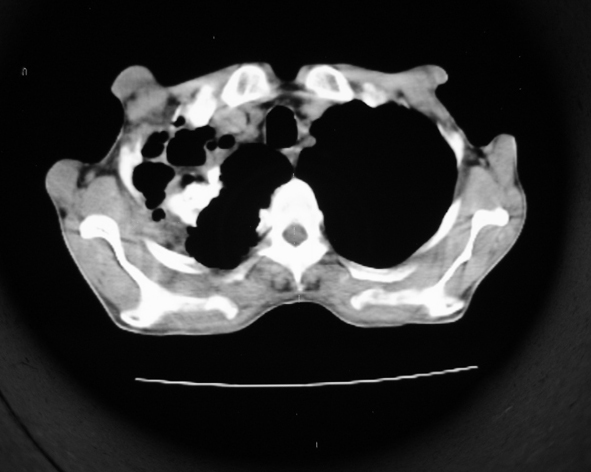

男53岁,咳嗽气短,以往身体健康.

右肺上叶多发多形态空洞及增殖灶,可见团块钙化,胸膜肥厚、粘连,考虑继发型肺结核可能性大

1.右肺上叶干酪性肺炎,2。肺气肿,肺大泡

右肺上中叶结核干酪性肺炎

右肺中上叶干酪性肺炎。

支持右上肺继发性肺结核并干酪性肺炎,右肺大泡,左肺代偿性气肿。